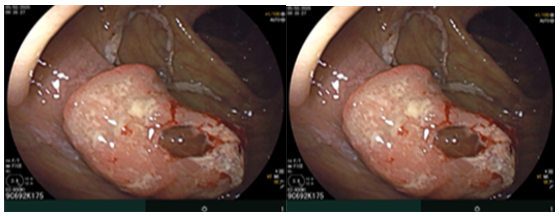

Sau đó bệnh nhân được nội soi dạ dày - đại tràng phát hiện đại tràng lên có khối lồi kích thước ~2.5cm, bề mặt nham nhở, cứng dễ chảy máu. Sinh thiết 03 mảnh. Giải phẫu bệnh: Ung thư biểu mô tuyến.

Hình 3. Tổn thương khối lồi xuất hiện ở vùng đại tràng lên

Nội soi đại tràng (thời điểm trước phẫu thuật T2/2025): Đại tràng lên có khối lồi kích thước ~2.5cm, bề mặt nham nhở, cứng dễ chảy máu.

Hình ảnh nội soi đại tràng thời điểm trước phẫu thuật.